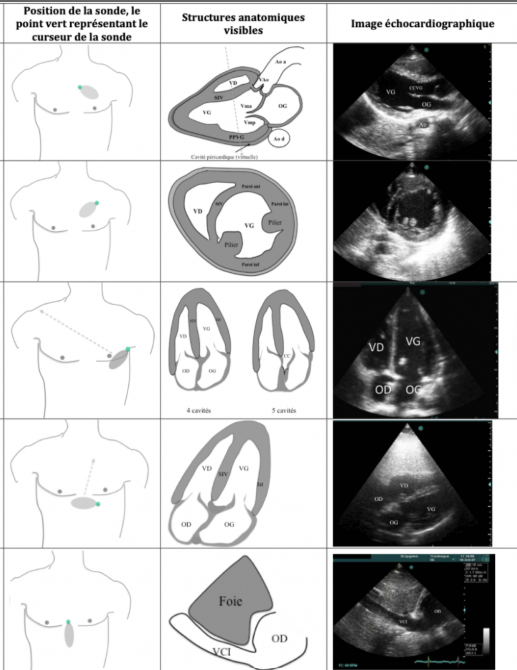

Pour chacune des coupes dire à quelle coupe échographique ça correspond